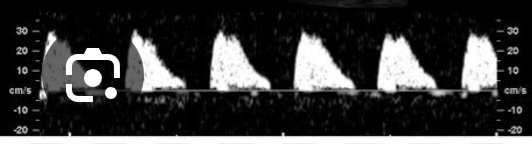

Q

O que significa essa imagem de doppler de arteria umbilical e qual a conduta?

Distole zero, singnifica um grande aumento da RP .

Conduta : interromper via cesariana > 32/34 sem